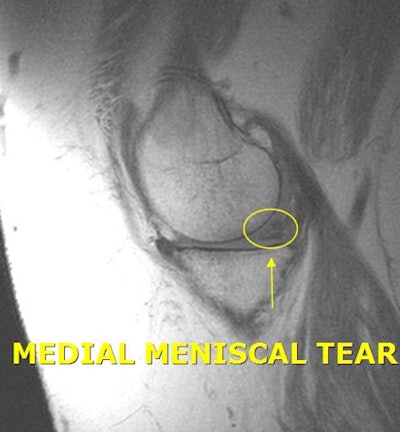

"We always hear about these injuries, but we really have no idea what they look like," Lalaji said. "We can only associate to them by, 'Yes, I know that is a knee.' If I can give people a snapshot or a little snippet of what [an injury] looks like and what normal looks like, the next time they hear about that injury they automatically can visualize [it]. "

Just to be clear, the clinical images posted on the website are not of the athletes. If the pictures were the athletes' actual images, it would be an obvious HIPAA violation. In fact, InsideInjuries.com specifically states that the images are only examples of the injury the athlete incurred, based on media reports.

"It is sort of a general diagnosis of the injury," Lalaji said. "It may be something like a hip sprain, which could be a hip flexor or something else. There are two or three different possibilities" posted on the site for an athlete's reported injury.

While the posted images are not detailed enough to be used as an educational tool for current or would-be radiologists, the site might be useful for an internist, family practitioner, or other healthcare specialist who is not in the field of imaging, Lalaji said.

"They may not know what some of these injuries look like," he added. "I think people outside of the field of radiology or orthopedic surgery might benefit from the site as a teaching tool."